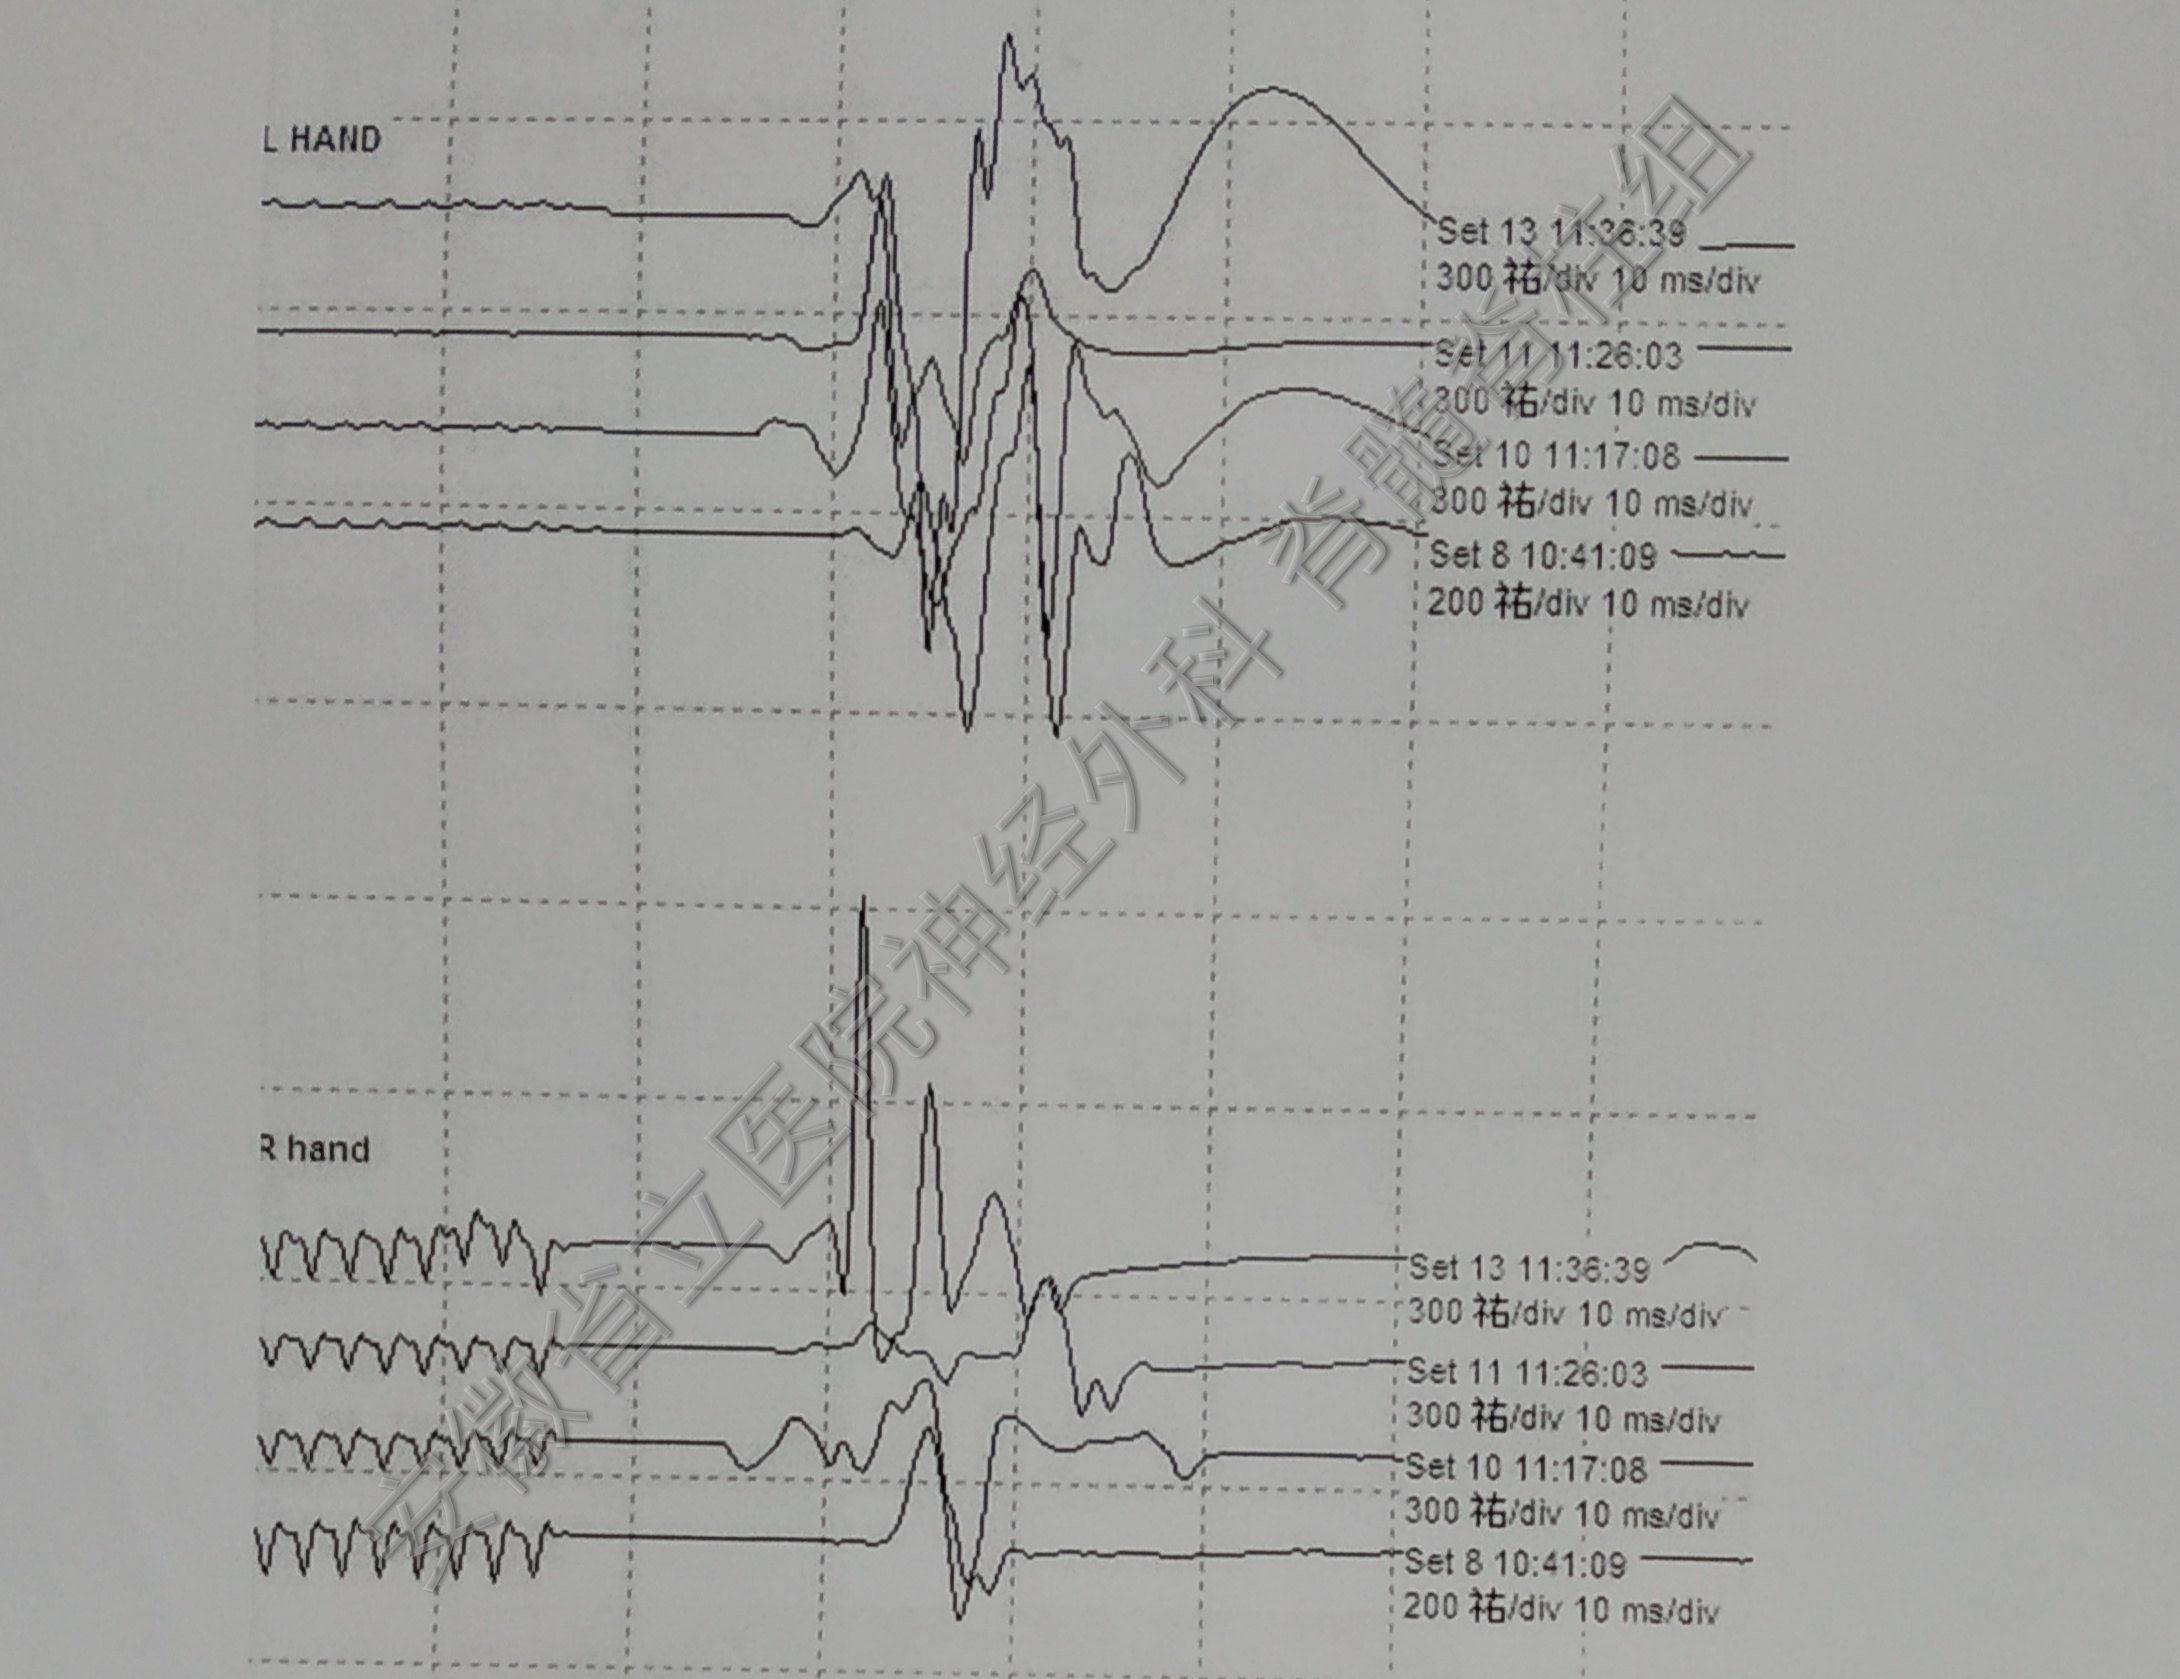

手术中全程电生理监测,保护脊髓神经功能完整。

肿瘤切除后予以椎板骨质复位,术后复查显示椎管内肿瘤全切除,骨质复位良好,手术部位解剖完整,患者恢复快,脊柱稳定性得以保证。

患者预后良好,术后肌力恢复很快,加强锻炼后肌肉萎缩逐渐恢复。